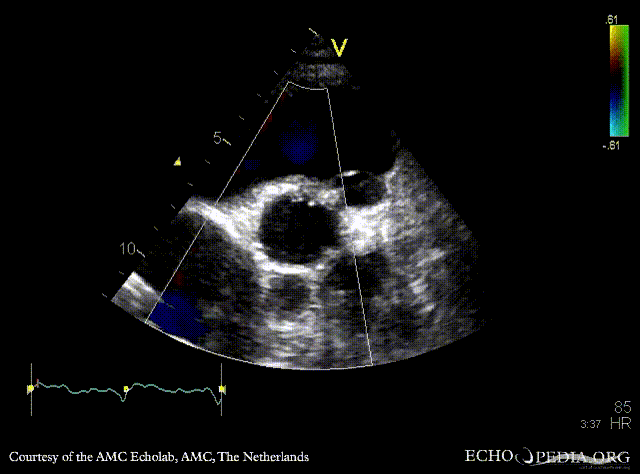

Abscess of aortic valve prosthesis

PSAX: mechanical aortic valve prosthesis, abscess cavity PSAX with Color Doppler